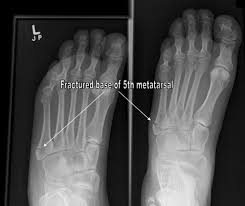

- Metertarsel fracture

Metatarsal fractures account for over 30% of traumatic foot injuries. Broken Metatarsals have been prominent across all professional sports in the past five years, with several high profile athletes suffering Metatarsal fractures. Metatarsal fractures can be caused by direct trauma, excessive rotational forces or overuse. The Fifth Metatarsal is the most commonly fractured Metatarsal.

The treatment of metatarsal fractures varies depending on the type and location of the fracture. If the fracture is due to direct trauma and the fracture fragments are well aligned then the treatment is immobilisation in a removable plastic cast and restricted weight bearing for 6 - 8 weeks. The same treatment is usually adequate for fractures of the other Metatarsal bones. However, stress fractures of the base of the Fifth Metatarsal sometimes show a poor healing capacity. For this reason, many orthopaedic consultants now favour surgical fixation.

Common Metatarsal Fracture Injury signs & symptoms:

- Severe foot pain.

- Swollen foot with bruising.

- Inability to walk on the broken foot.